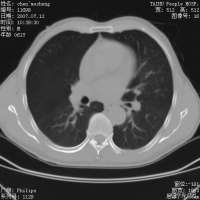

内火有着更深层次的意思,也就是上火的一些广义的症状,比如胃火可以有胃疼、大便干等症状,肺火

咯血X光图

以有咯血、咳嗽、黄痰等症状,肝火会有一些烦躁、失眠、女性会有乳房胀痛等。